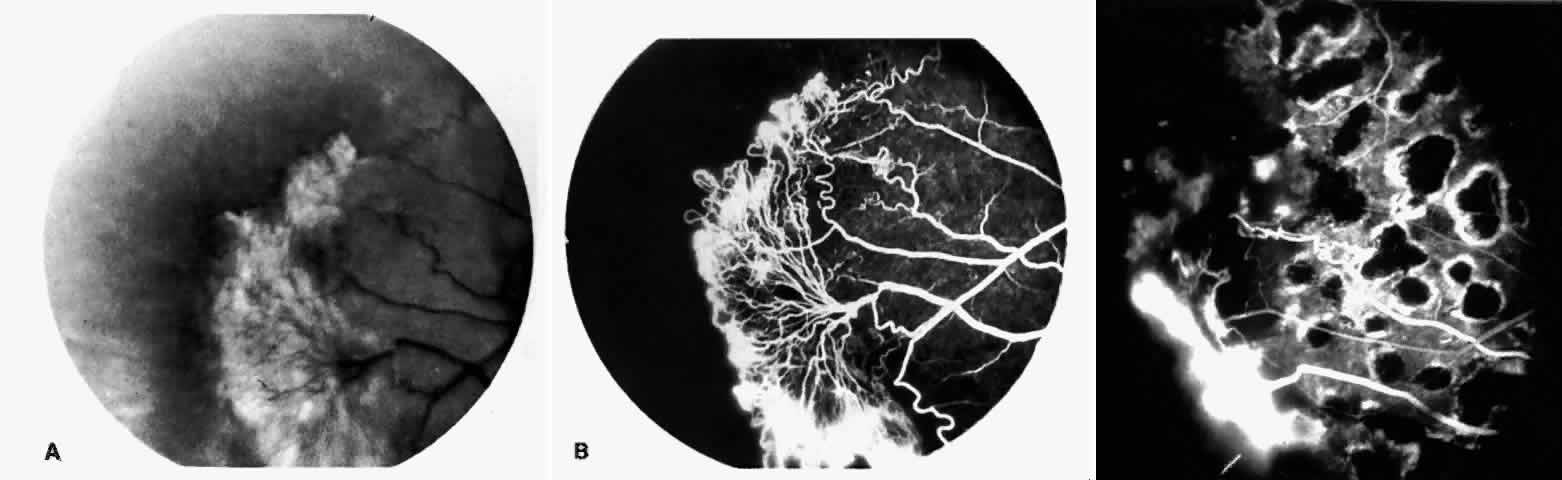

STAGE III: PRERETINAL NEOVASCULARIZATION (PROLIFERATIVE SICKLE RETINOPATHY). “Sea fan”-shaped neovascularization typically develops on the venular side of an arteriolar-venular anastomosis, mimicking the normal development of retinal capillaries (Fig. 24).125 A lowered oxygen tension and angiogenic factors released on the venular side may be the stimulus for neovascular growth.125,126 In most instances, the direction of growth is toward the ora serrata, from the perfused retina toward the nonperfused retina. Presumably, this represents an abortive attempt to revascularize the nonperfused retina, initiated by vasoproliferative factors.

Fig. 24. A. Photograph of the peripheral retina, demonstrating several small fibroglial membranes. B. Fluorescein angiogram corresponding to A, showing multiple arteriolar-venular anastomoses with early sea fan formation. C. Photograph of the same area 2 years later demonstrates more fibroglial membranes. D. Fluorescein angiogram corresponding to C shows new sea fans caused by an arteriolar-venular anastomosis (curved arrow). Large arrow (A through D) identifies corresponding arteriolar bifurcation.

The characteristic neovascular lesions of PSR are called sea fans because they resemble the marine invertebrate Gorgonia flabellum.70 They tend to occur more commonly in the temporal periphery, but they have been reported to occur in the temporal macula in the presence of extensive nonperfusion.130,133 Initially they grow on the surface of the retina, but they often become elevated into the vitreous and adhere to a partially detached posterior hyaloid.114 It may be difficult to visualize small sea fans ophthalmoscopically; however, fluorescein angiography clearly demonstrates leakage of dye into the vitreous (Fig. 25). The feeding arteriole is usually more tortuous than the draining venule (Fig. 26). Early on, the neovascular lesion is fed by a single arteriole and drained by a single venule, but with time, additional arterioles and venules become arborized within the lesion (Fig. 27).129 Growth of the sea fan often occurs circumferentially, rather than radiallyÜmh- 1Ý, toward the ora serrata. Progressive circumferential growth may lead to neovascular lesions extending around the entire periphery. As it matures, a white fibroglial mantle often covers the neovascular tissue (Color Plate 2B).

Fig. 25. Fluorescein angiogram of early proliferative sickle retinopathy arising from an arteriolar-venular anastomosis in an area of irregular peripheral capillary border. Note that this area of qualitatively abnormal peripheral capillary border is in the same eye with a qualitatively normal peripheral retinal vasculature, as demonstrated in Figure 23.

Fig. 26. A. Arterial filling phase of the fluorescein angiogram of a sea fan demonstrates tortuosity of the feeding arteriole. B. Early arteriolar-venular filling phase demonstrates straightening of the draining venule. Note that this sea fan is adjacent to the qualitatively normal peripheral retinal vasculature demonstrated in Figure 23.

Fig. 27. A. Photograph of sea fan neovascularization with hemorrhages at the margins and a white line demarcating perfused and nonperfused retina. B. Fluorescein angiogram shows multiple feeding arterioles and draining venules.